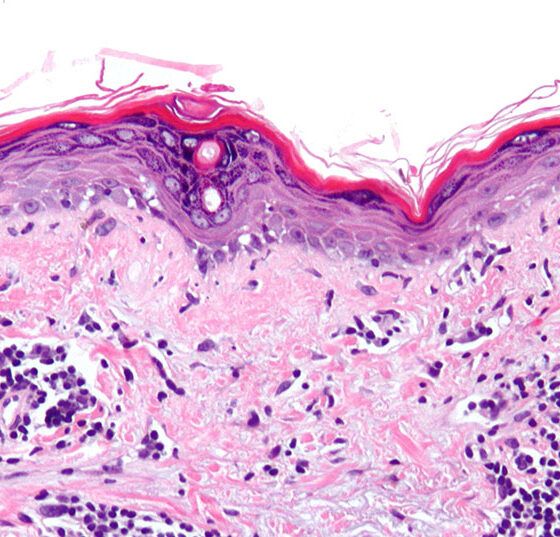

• Systemischer Lupus erythematodes

Die Zukunft gehört der Präzisionsmedizin

Die vielfältigen Krankheitsmanifestationen des systemischen Lupus erythematodes (SLE) sind im Wesentlichen eine Folge von Autoantikörpern, Immun­komplexen und Zytokinen. Neue Therapien greifen gezielt in die Immunpathogenese der komplexen Autoimmunerkrankung ein. Lange...…